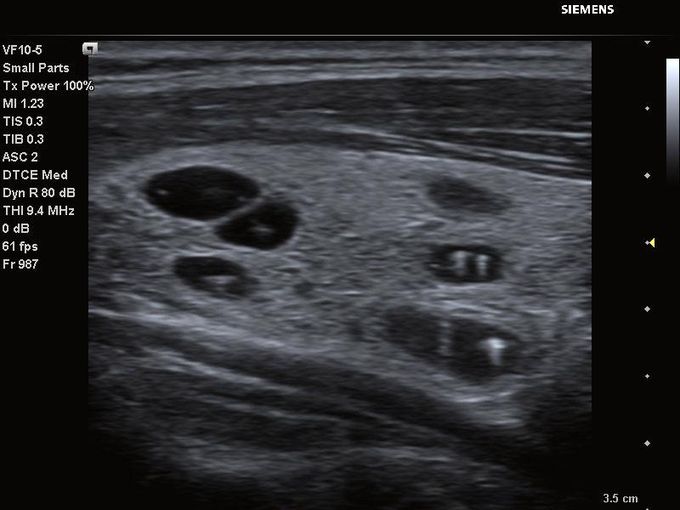

Кроме новой техники, можно заказать восстановленные медицинские системы: ультразвуковые сканеры, томографы, флюороскопы, ангиографы и хирургические установки С-дуга.